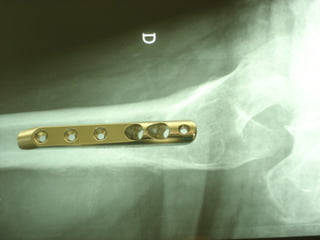

The GOTFRIED plate

La placca a compressione percutanea (PC.C.P.) di Gotfried è un mezzo di sintesi studiato per assicurare un “impattamento controllato” delle fratture pertrocanteriche grazie alle due viti telescopiche prossimali che garantiscono una ottima stabilità rotazionale

Con la placca di Gotfried non si è mai riscontrato un danno iatrogeno del muro laterale e nessun collasso della frattura.Ciò è dovuto al fatto che i fori per l’applicazione delle due viti prossimali sono di piccolo diametro (9 mm) rispetto ai 16-32 mm necessari per introdurre la vite cefalica di un chiodo endomidollare o di una vite-placca a compressione.

La placca PC.C.P. viene inoltre applicata per via percutanea attraverso due piccole incisioni ottenendo in tal modo un minimo trauma chirurgico ed una  perdita di sangue estremamente ridotta in pazienti che per l’età  sono già in condizioni  critiche